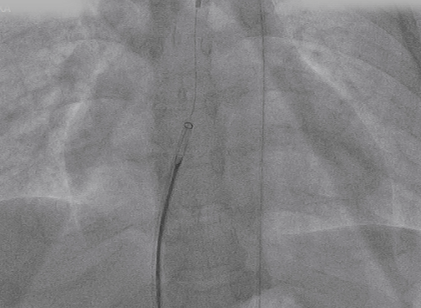

导丝通过主动脉窦瘤破口(左);导丝置于下腔静脉(右)

圈套器抓取导丝建立完整轨道